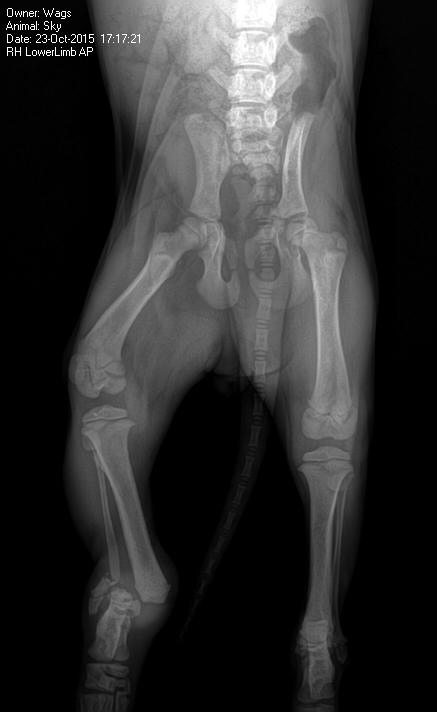

In a horrible twist of fate, Sky somehow has had to avoid euthanasia at the same shelter in North Carolina twice. First she was adopted from the shelter directly to a forever home, which turned out to be a

temporary hell, where she suffered broken ribs, a broken leg and fell ill with parvovirus.

nd another injured dog the same night. It was recommended that Sky be euthanized due to all the pain associated with her injuries and the parvovirus that rendered her too weak for surgery. Despite all of this, Sky continued to wag her tail!

Instead, WAGS fought harder to keep her alive and took her to an emergency vet in North Carolina where she was immediately treated for parvo. Things were looking good the next week and the vet opted to try to save her leg and put it in a splint.